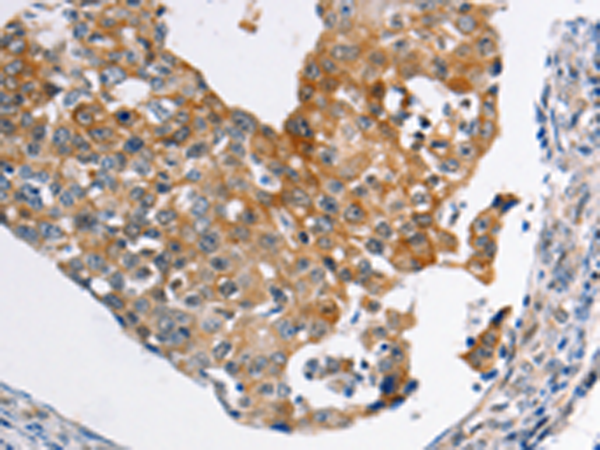

分类: 科研抗体货号: P11029别名: MLP2, MRP3, ABC31, MOAT-D, cMOAT2, EST90757应用: IHC反应种属: Human, Mouse